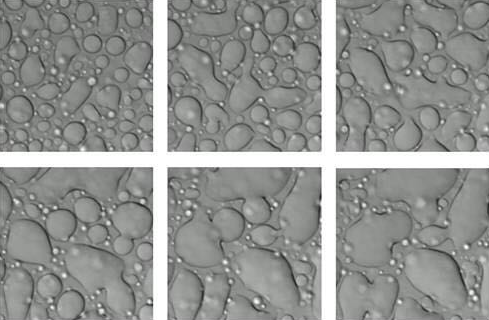

显微镜下,通过液相分离熔合和成长形成富含蛋白质的液滴。这种液滴与细胞内某些类型的无膜细胞器相似。圣裘德科学家获得的证据表明,与ALS及相关退行性疾病有关的毒性肽类会干扰正常的液相分离并扰乱众多无膜细胞器的组装和功能。

(摄制人员:Amandine Molliex和Jamshid Temirov)